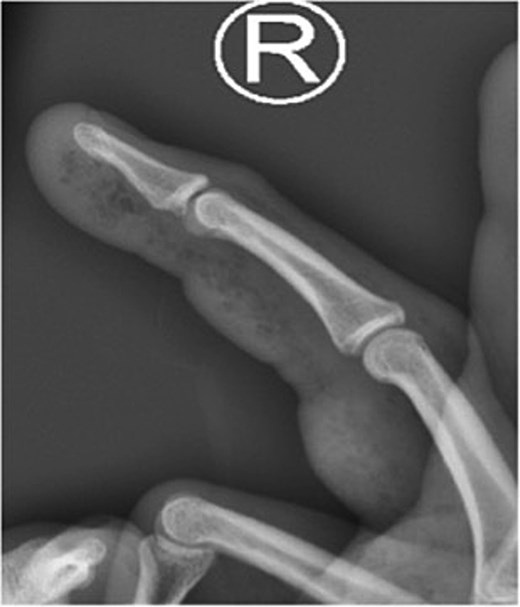

Initial presentation (Fig. 1) with accompanying X-ray (Fig. 2) and intra op image during first debridement (Fig. 3).

X-ray image of patient one showing injected material into volar surface of his digit.